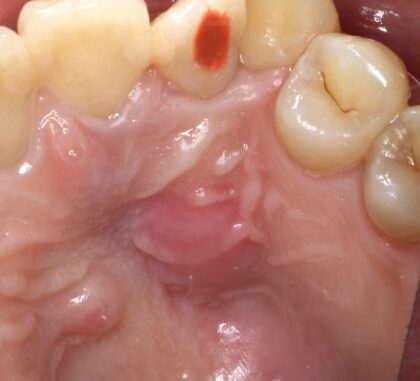

症例3

| 項目 | 詳細 |

|---|---|

| 患者様データ | 50代 女性 |

| 来院時の主訴 | 「左下の歯茎が腫れている。」 |

| 医院の診断 | 慢性根尖性歯周炎 |

| 通院期間 | 4ヶ月 |

| 来院回数 | 6回(定期的なチェック含む) |

| 治療費 | 220,000円(税抜) 《内訳》 精密根管治療80,000円、ファイバーポストコア20,000円、セラミック治療120,000円 |

| リスクと副作用 | ①根管治療歯は長期的には破折するリスク ②メインテナンスが必要 |

| ココがこだわりのポイント☝ |

ラバーダム防湿とマイクロスコープを使用して丁寧に治療を行いました。 |